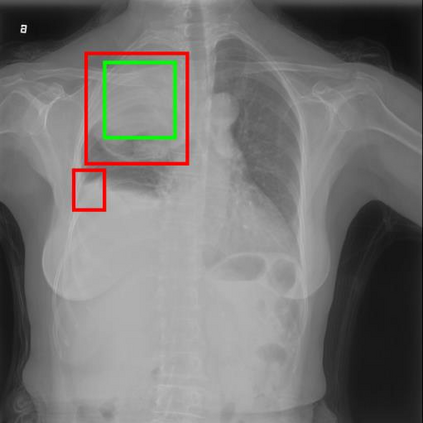

Chest X-ray (CXR) is the most typical diagnostic X-ray examination for screening various thoracic diseases. Automatically localizing lesions from CXR is promising for alleviating radiologists' reading burden. However, CXR datasets are often with massive image-level annotations and scarce lesion-level annotations, and more often, without annotations. Thus far, unifying different supervision granularities to develop thoracic disease detection algorithms has not been comprehensively addressed. In this paper, we present OXnet, the first deep omni-supervised thoracic disease detection network to our best knowledge that uses as much available supervision as possible for CXR diagnosis. We first introduce supervised learning via a one-stage detection model. Then, we inject a global classification head to the detection model and propose dual attention alignment to guide the global gradient to the local detection branch, which enables learning lesion detection from image-level annotations. We also impose intra-class compactness and inter-class separability with global prototype alignment to further enhance the global information learning. Moreover, we leverage a soft focal loss to distill the soft pseudo-labels of unlabeled data generated by a teacher model. Extensive experiments on a large-scale chest X-ray dataset show the proposed OXnet outperforms competitive methods with significant margins. Further, we investigate omni-supervision under various annotation granularities and corroborate OXnet is a promising choice to mitigate the plight of annotation shortage for medical image diagnosis.